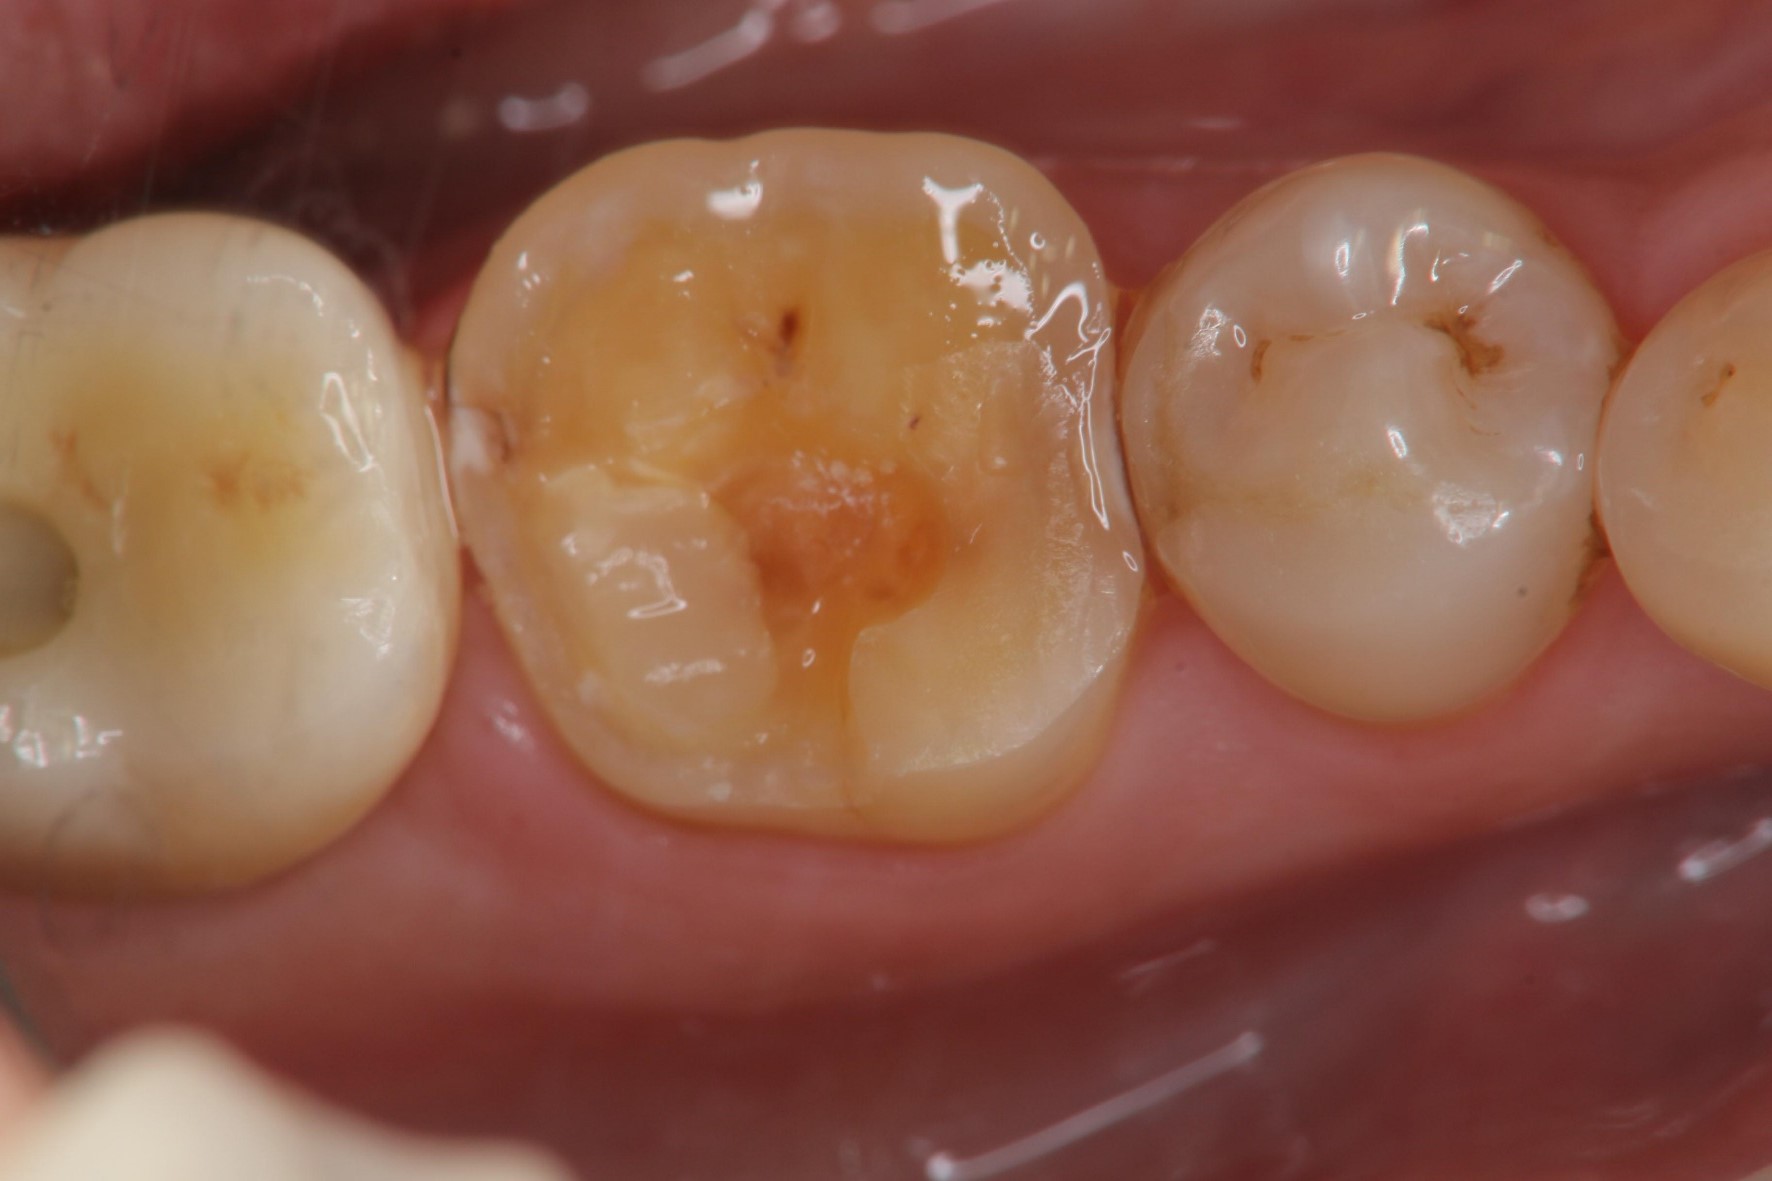

治療前,二次蛀牙,咬頭受損

蛀牙未到牙髓

冠塊體體製備